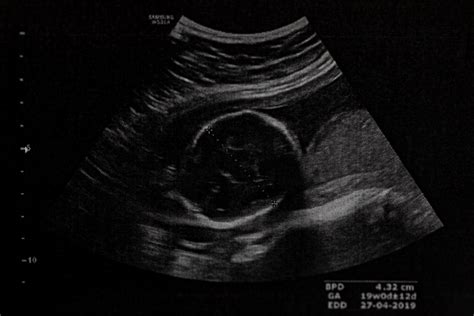

Ďalším spôsobom je ultrazvukové vyšetrenie, najpresnejšie v prvom trimestri (10. až 12. týždeň). Ak je rozdiel medzi termínom podľa PM a ultrazvuku väčší ako 7 dní, riadi sa tehotenstvo termínom určeným ultrazvukom.